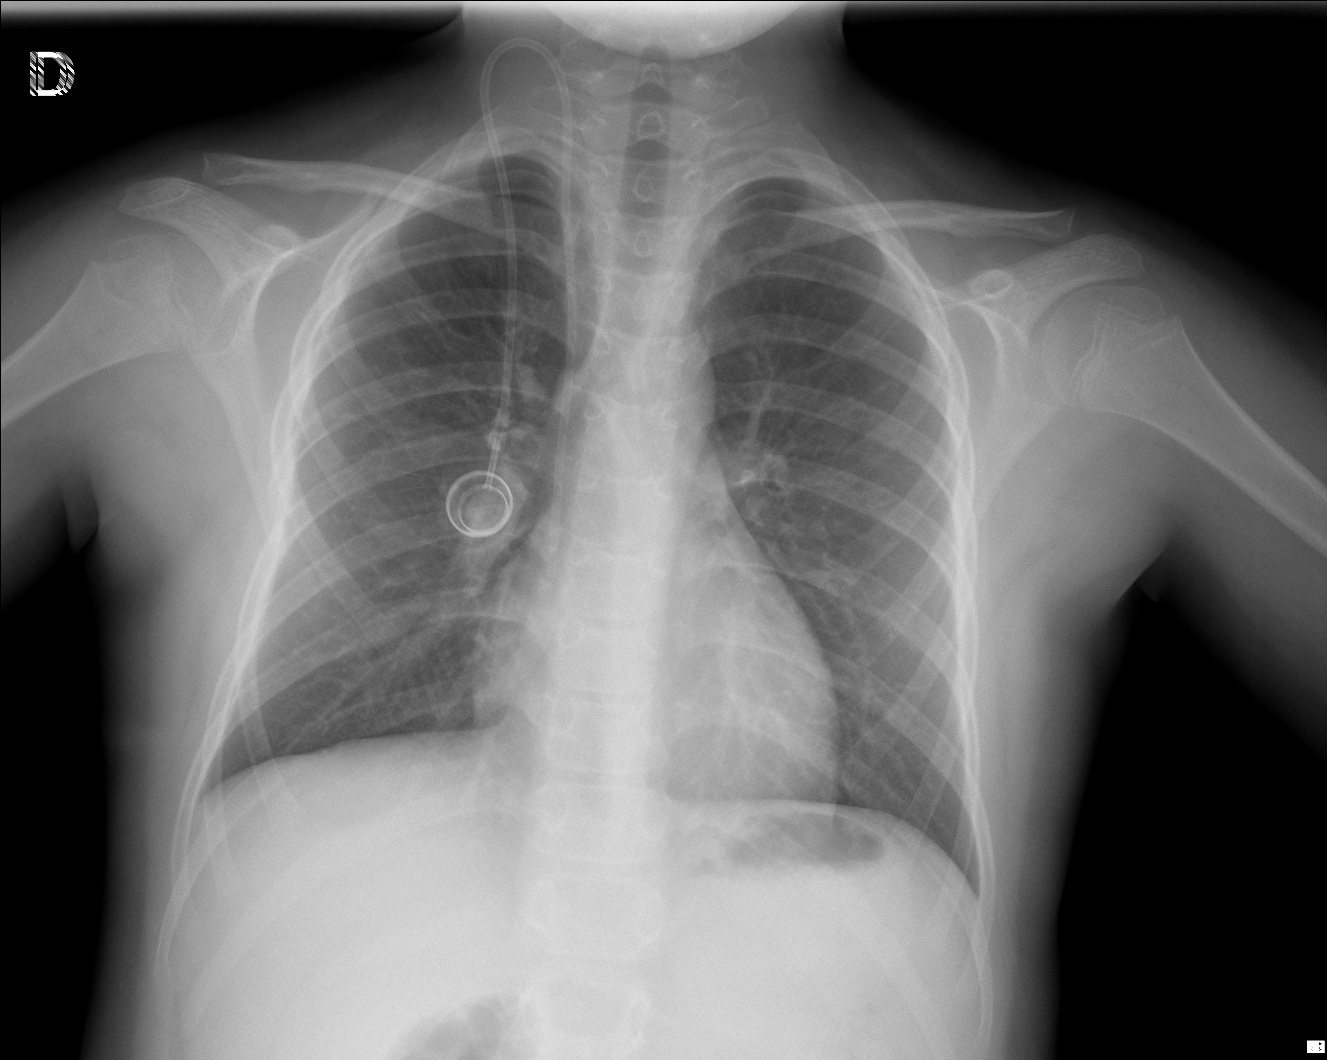

CASO: Revisión en paciente con tratamiento quimioterápico.

Hallazgos:

- Reservorio subcutáneo en hemitórax izquierdo con bucle del catéter a nivel subclavio. Extermo del catéter en vena cava superior.